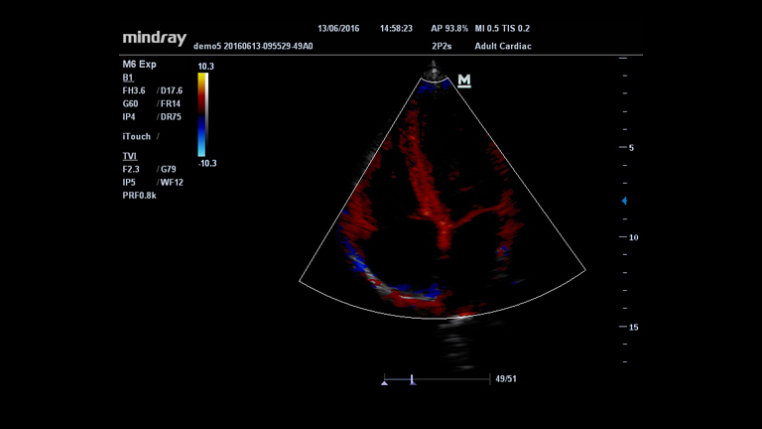

iTouch™ (automatyczna optymalizacja obrazu)

Funkcja ta pozwala uzyskać natychmiastową automatyczną optymalizację obrazu w trybach B, Kolorowego Dopplera i PW (Spektralnego Dopplera Fali Pulsacyjnej) poprzez naciśnięcie jednego klawisza.